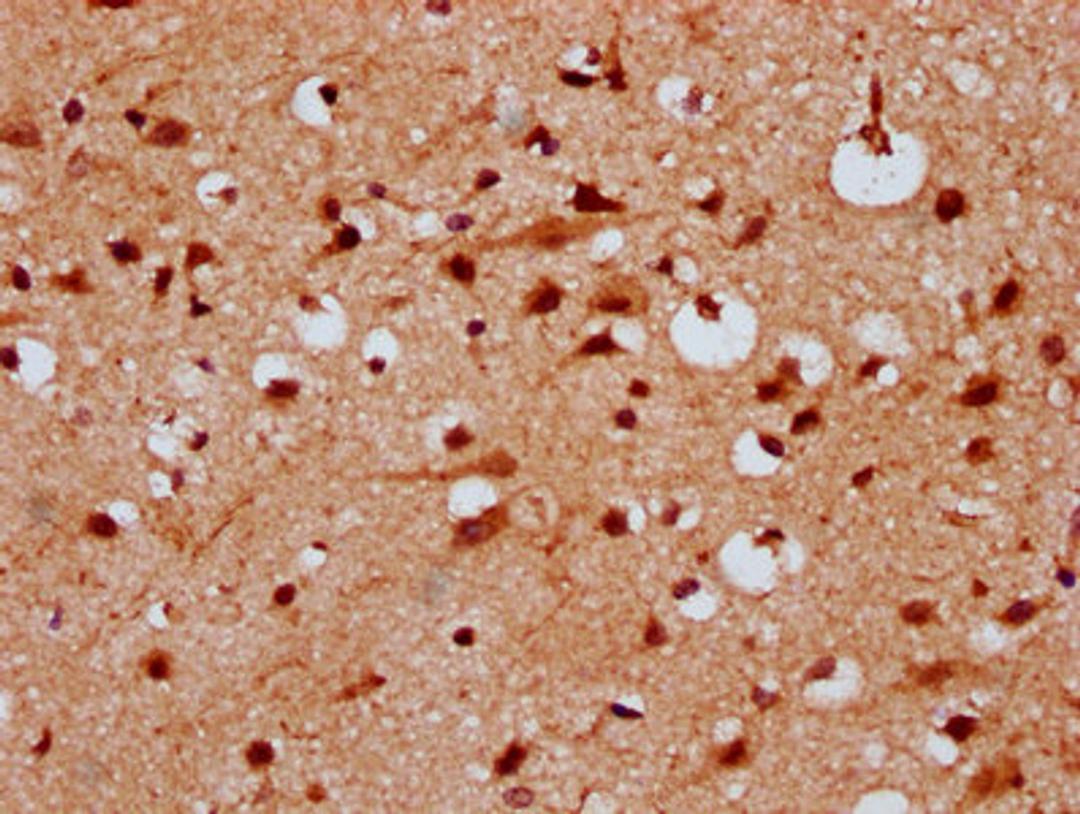

IHC image of CSB-PA22879A0Rb diluted at 1:300 and staining in paraffin-embedded human brain tissue performed on a Leica BondTM system. After dewaxing and hydration, antigen retrieval was mediated by high pressure in a citrate buffer (pH 6.0). Section was blocked with 10% normal goat serum 30min at RT. Then primary antibody (1% BSA) was incubated at 4°C overnight. The primary is detected by a biotinylated secondary antibody and visualized using an HRP conjugated SP system.